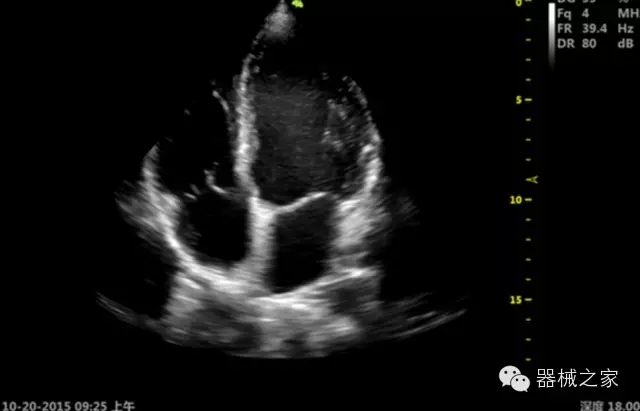

臨床圖片賞析

產(chǎn)品特點

·心功能綜合指數(shù)(TEI指數(shù)):用于左、右心室整體心臟收縮舒張功能評估的測量方法;

·全方位可調(diào)M型:有利于更好的觀察心腔大小及室壁階段性運動的異常情況;

·組織多普勒成像(TDI):TDI可定量評價心肌運動,判斷是否有局部病變,還可評價早期的舒張功能;